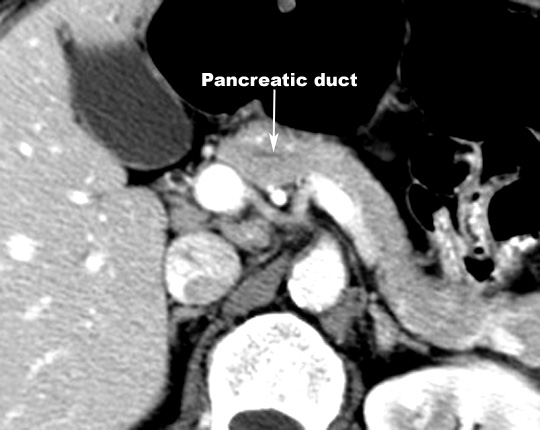

- The common bile

duct traverses through the head of the pancreas and joins with the

pancreatic duct at the ampulla of Vater to empty bile into the second or

descending part of the duodenum.

- Both

the pancreatic duct of Santorini and Wirsung drain the exocrine pancreas.